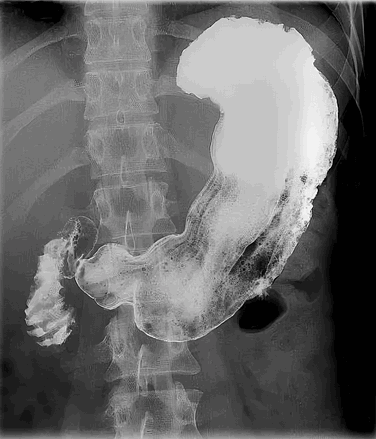

На контрастном снимке видно, что кардиа, свод и тело желудка образуют нисходящую часть тени, а пилорическая часть желудка — восходящую часть тени (рис. 126, 127). Соотношения нисходящей и восходящей частей тени желудка у разных людей неодинаковы; можно наблюдать три основных формы и положения желудка.

Представление о тонусе желудка в рентгеновском изображении дает характер «развертывания» стенок желудка при заполнении его пищей. Натощак желудок находится в спавшемся состоянии, а при попадании в него пищи начинает растягиваться, плотно охватывая свое содержимое. В желудке с нормальным тонусом первые порции пищи располагаются в виде треугольника, обращенного основанием кверху, к газовому пузырю. Воздушный пузырь, ограниченный сводом желудка, имеет форму полушария.

При пониженном (в пределах нормы) тонусе желудка треугольник, образуемый пищей, имеет удлиненную форму с острой вершиной, а воздушный пузырь напоминает вертикальный овоид, суживающийся книзу. Пища, не задерживаясь, падает на большую кривизну, как в вялый мешок, оттягивает ее книзу, вследствие чего желудок удлиняется и приобретает форму чулка и вертикальное положение.Форма желудка изучается при полном контрастном его наполнении. При частичном наполнении можно видеть рельеф слизистой оболочки. Складки слизистой желудка образуются при сокращении lamina muscularis mucosae, изменении тургора и набухании тканей, при весьма рыхлой структуре под-слизистой основы, допускающей подвижность слизистой оболочки относительно других слоев (рис. 131).

Преобладающая картина рельефа слизистой в различных отделах желудка такова: в pars cardiaca — сетчатый рисунок; вдоль curvatura minor — продольные складки; вдоль curvatura major — зубчатый контур, так как складки в corpus ventriculi — продольные и косые; в antrum pyloricum — преиму* щественно продольные, а также радиальные и поперечные.

Вся эта картина рельефа слизистой обусловлена складками задней стенки, так как на передней стенке их мало. Направление складок соответствует продвижению пищи, поэтому рельеф слизистой оболочки крайне изменчив.